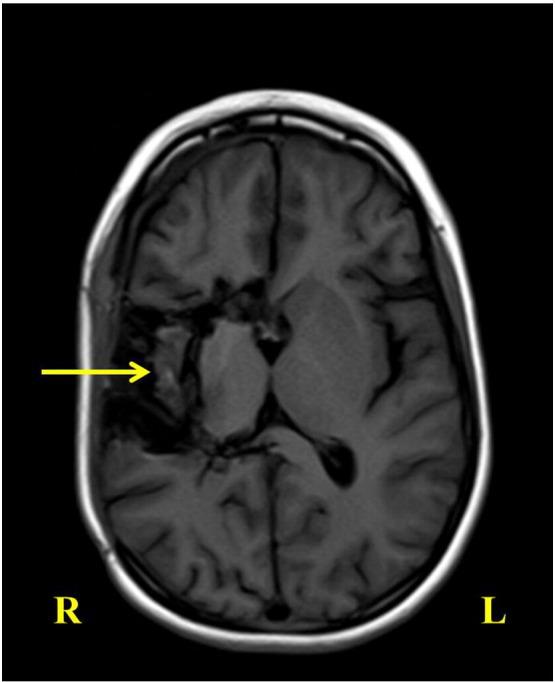

A 7-year-old previously healthy girl presented with a left-sided focal seizure without impaired consciousness and subsequently developed epilepsia partialis continua. Initial MRI was normal, and the subsequent images only showed a focal T2/FLAIR hyperintense area without cortical atrophy. She was diagnosed with Rasmussen syndrome by pathology and promptly treated with functional hemispherotomy. Rasmussen syndrome is a rare progressive neurological disorder, the only definitive cure for which is hemispheric disconnection. The disease presents a management dilemma, especially early in disease course without characteristic neuroimaging features. A high index of suspicion, multidisciplinary approach, and clear timely communication with the family are critical.

一名7岁的既往健康女孩出现左侧局灶性癫痫发作,意识未受损,随后发展为持续性部分性癫痫。初次MRI检查正常,后续影像仅显示一个局灶性T2/FLAIR高信号区,无皮质萎缩。经病理诊断为拉斯穆森综合征,并立即接受了功能性大脑半球切除术治疗。拉斯穆森综合征是一种罕见的进行性神经疾病,唯一的确切治疗方法是大脑半球离断术。该疾病带来了治疗难题,尤其是在病程早期没有特征性神经影像学表现时。高度的怀疑指数、多学科方法以及与家属清晰及时的沟通至关重要。